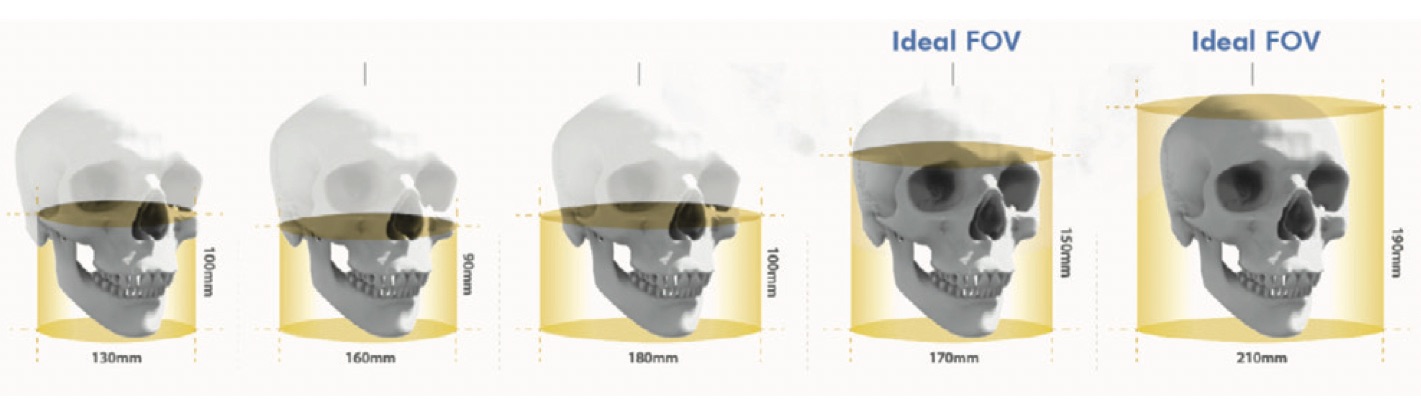

In addition, in a CBCT system, the X-ray beam is a conical shape and produces a cylindrical or spherical data volume, known as the FOV (field of view). The size of the FOV differs between scanners, with some capable of capturing the entire maxillofacial skeleton. Also some CBCT machines can adjust the height of the cylindrical FOV to capture a single area, which reduces the radiation dose to the patient.

Schematic demonstration of the different sizes of FOV in CBCT.

According to the FOV we can classify CBCT equipment into large FOV systems (15-30.5 cm) and limited FOV systems (4 to 8 cm). This is important because:

The higher the FOV:

- More extensive imaging of the anatomical area.

- Higher radiation exposure.

- Lower image resolution.

A lower FOV:

- Imaging of a small part of the anatomical area<./li>

- Lower radiation exposure.

- Higher resolution images.

For dentistry applications where maximum detail of structures is not required, but instead a more meaningful representation of the face, such as orthodontics or implant planning, a CBCT scanner with large or moderate FOV may be more effective. But, for example, when diagnosing dental alterations, a more accurate image of a small part is needed, and in this case the use of a limited FOV CBCT system would be more appropriate. Let's take a closer look at the different applications of a CBCT scanner in the dental practice: